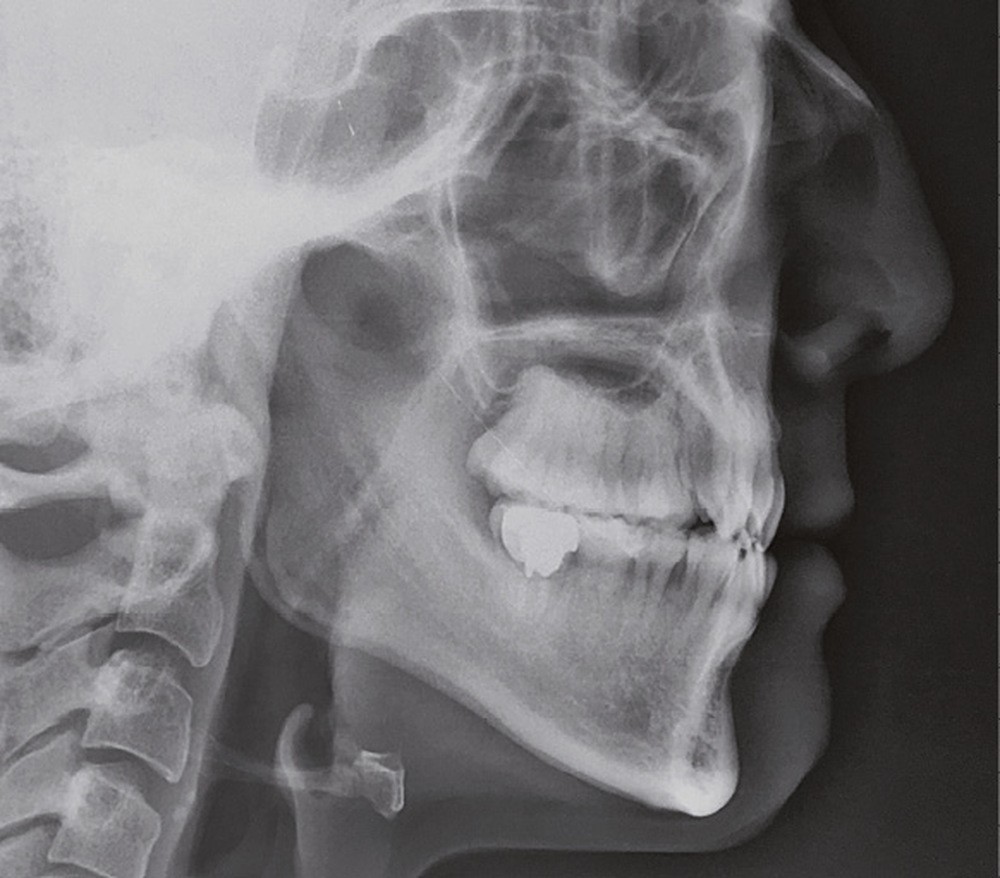

Sur le plan squelettique, on retrouve une classe III de Ballard par hypomaxillie, dans un schéma facial hyperdivergent.

Sur le plan dentaire, la patiente est en classe III droite et gauche, canine et molaire de 6 mm, avec une occlusion inversée antérieure localisée à 11, 12 et 22. Elle présente une dysharmonie dents-arcades sévère, une agénésie d’une incisive mandibulaire est à signaler, et les troisièmes molaires ont été extraites à l’âge de 21 ans.

Au niveau fonctionnel, on note un bruxisme statique avec contact permanent entre les dents maxillaires et mandibulaires. La patiente présente des prématurités en relation centrée sur les incisives, le guidage en propulsion est perturbé et des interférences multiples sont retrouvées en latéralités droite et gauche.